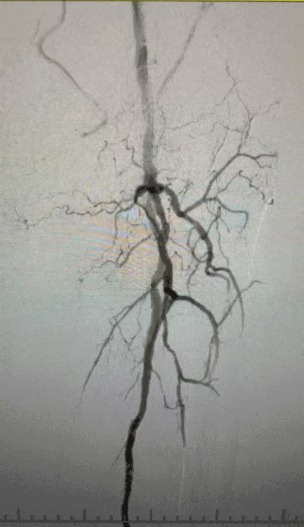

Клинические выводы

· Физическое обследование: слабые импульсы бедренной кости; отсутствие импульсов подколенных и спинного ног; изъязвление на первом левом пальце ноги; некроз на первом и втором пальцах правой ноги

· Предоперационная визуализация: тяжелый диффузный кальцинированный стеноз в двусторонних артериях нижних конечностей.

Лечебный подход

Учитывая сложное сосудистое состояние, мы выбрали систему периферийного расширительного баллона IVL ThorCrack. Из-за ограниченной толерантности пациента были выполнены поэтапные интервенционные процедуры на обеих нижних конечностях.

Хирургический результат

Пост-процедура, артериальный стеноз улучшился значительно, кровоток увеличился, и температура кожи поднялась. Послеоперационных осложнений не произошло. И пациент, и хирургическая команда были очень довольны результатами.